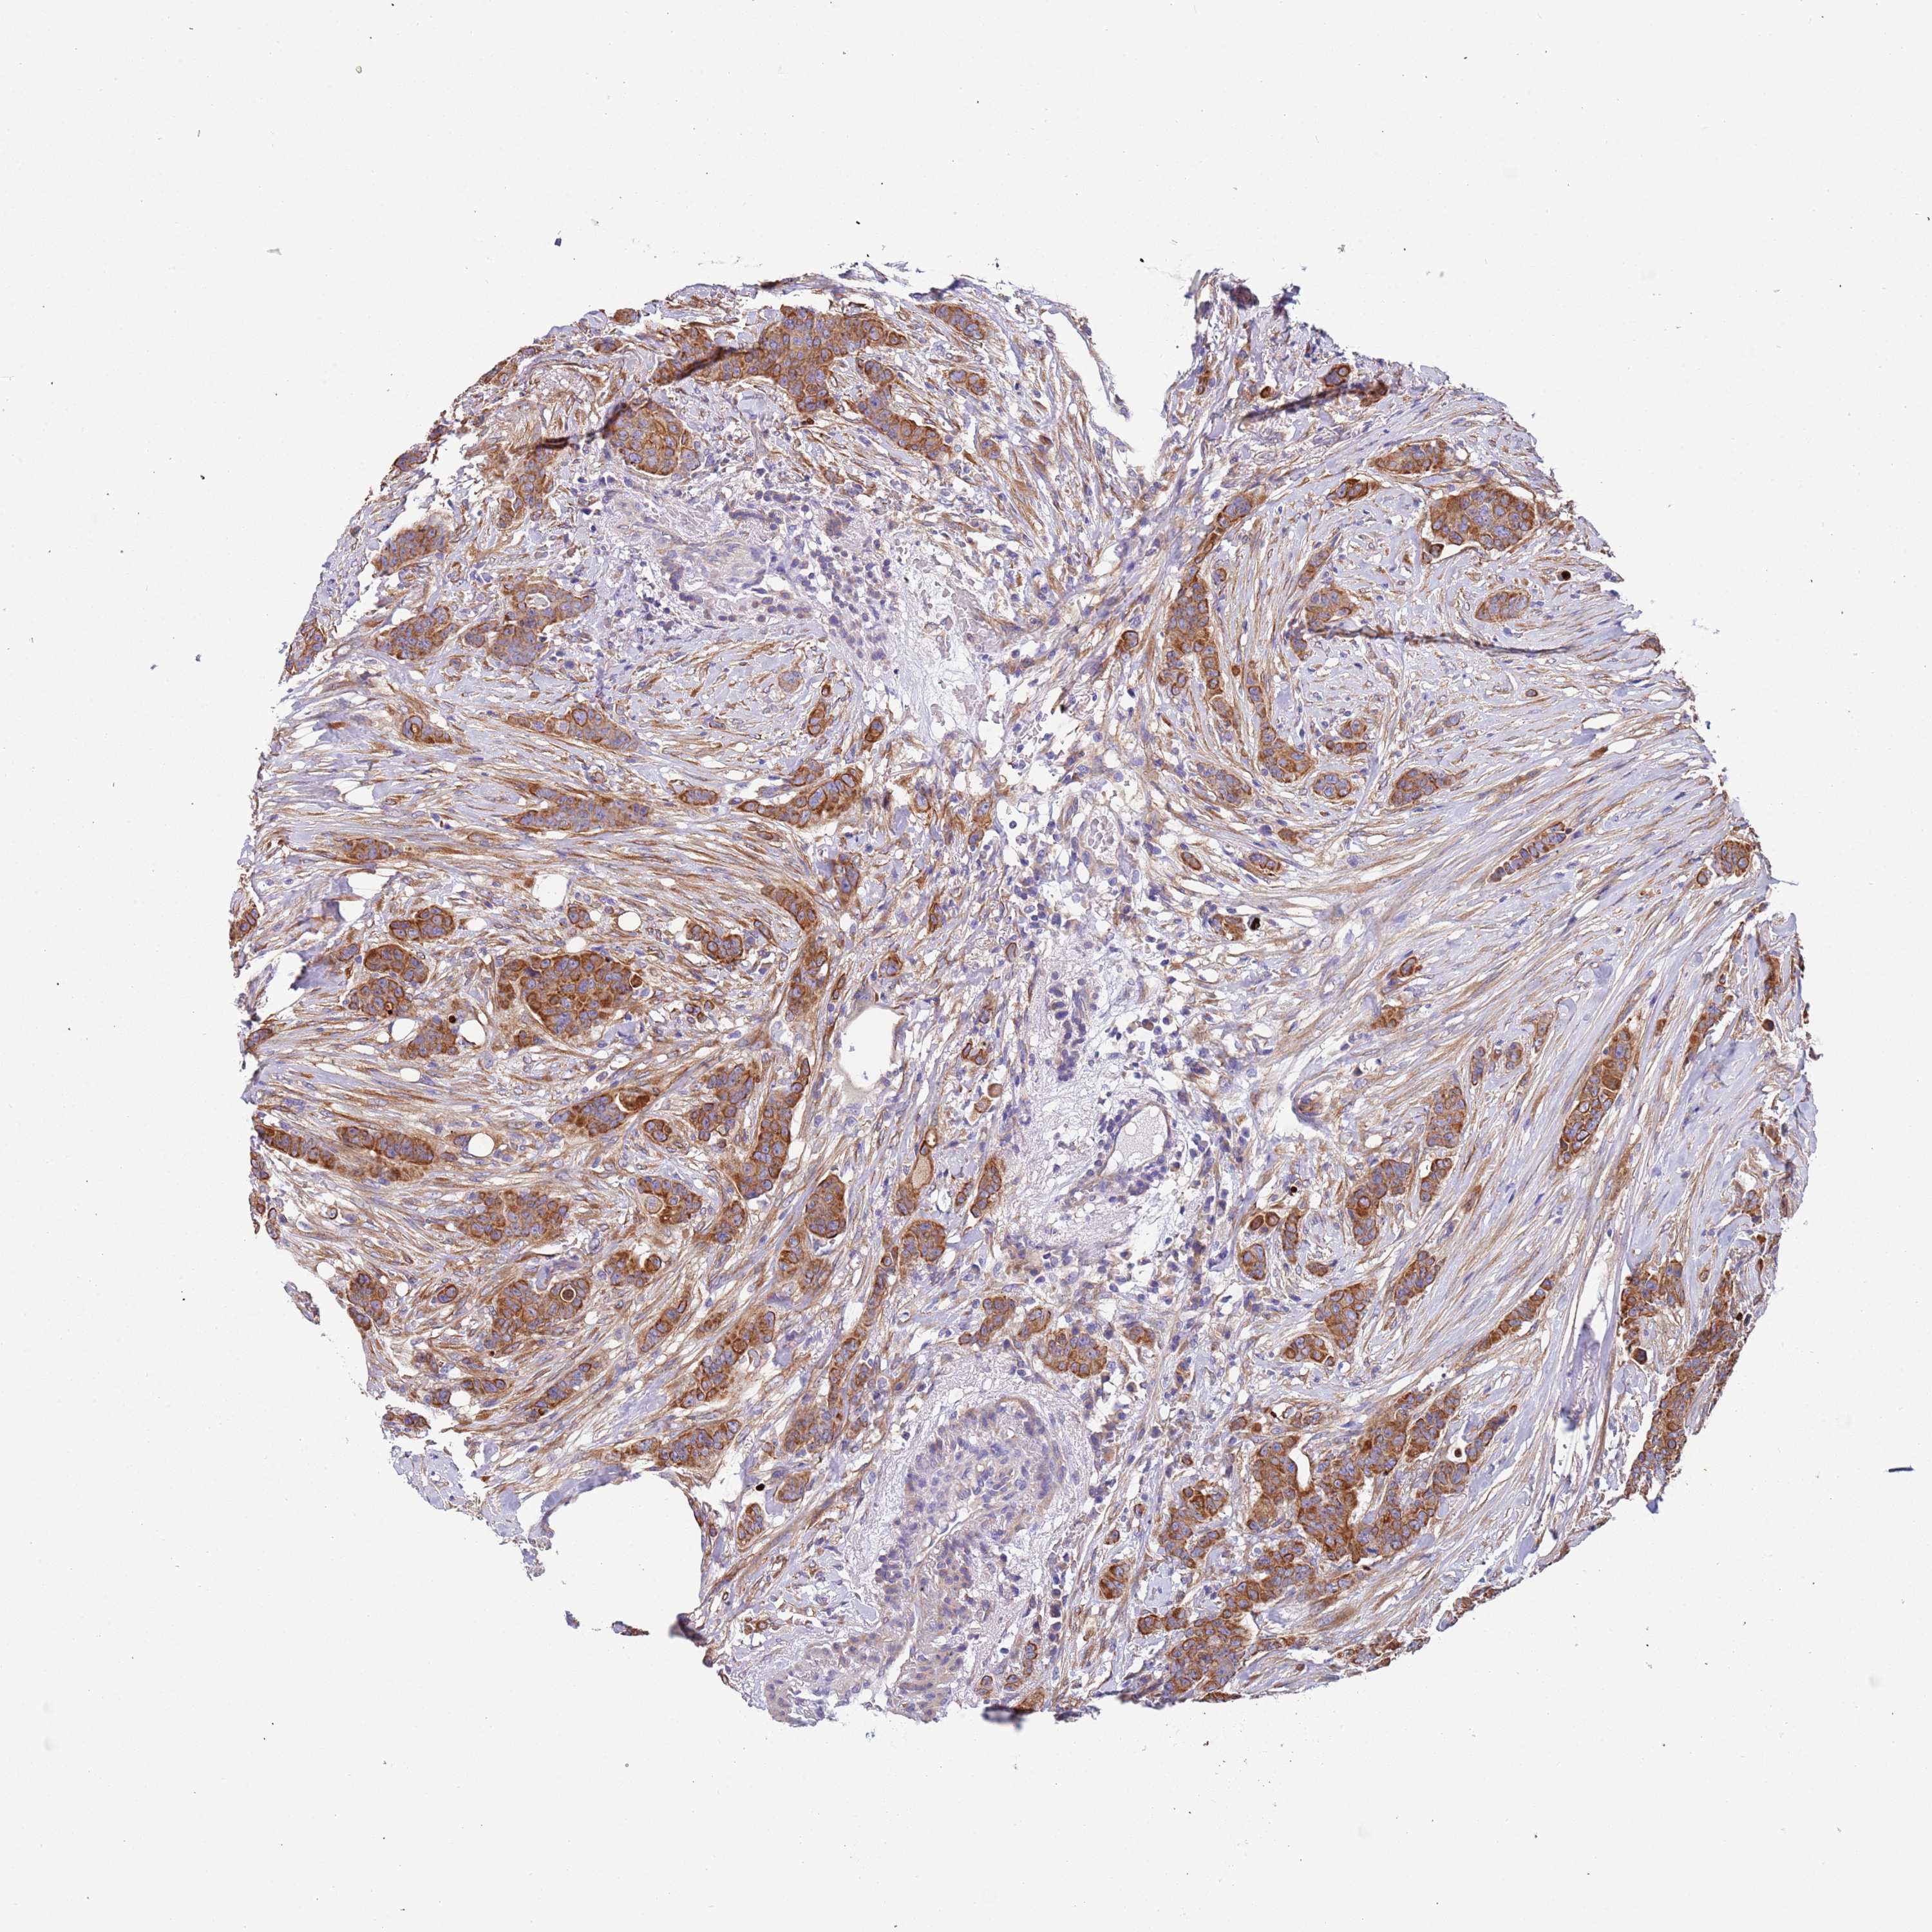

CANCER BREAST CANCER Show tissue menu

BRCA TCGA BRCA VALIDATION PROTEIN EXPRESSION

ANTIBODIES

AND

VALIDATION